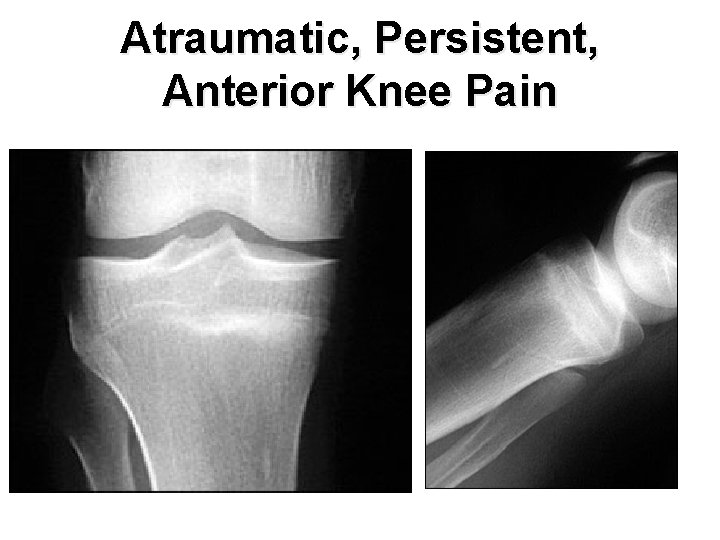

Persistent Anterior Knee Pain n A 20 year old military recruit presented for follow up of anterior knee pain. Previously, he presented with three weeks of right knee pain without trauma, swelling, locking, or instability. At that visit, he was referred for physical therapy, but the knee did not improve during treatment. On recent examination, the patient had a positive “theater sign” (i. e. , knee pain upon arising after prolonged sitting), positive patellar compression and inhibition tests, stable ligaments, pain with Mc. Murray's test, and tenderness of the medial tibial plateau.

Atraumatic, Persistent, Anterior Knee Pain

Discussion n The answer is E: proximal tibial stress fracture. Most tibial stress fractures occur in the tibial diaphysis. However, proximal tibial stress fractures, typically involving the medial condyle, can occur in athletes. Stress fractures may result from weaker bone that fails under normal loading (i. e. , an insufficiency fracture) or normal bone that fails under new or increased repetitive loading (i. e. , a fatigue fracture). Athletes are more likely to experience a fatigue fracture; military recruits are also at risk. Drabicki RR, Greer WJ, De. Meo PJ. Stress fractures around the knee. Clin Sports Med. 2006; 25: 105– 15. Raasch WG, Hergan DJ. Treatment of stress fractures: the fundamentals. Clin Sports Med. 2006; 25: 29– 36.

Discussion n Medical history that suggests a stress fracture will include persistent pain following an acute increase in physical activity (i. e. , time, distance, or pace). Physical examination may reveal tenderness at or near the medial joint line, tenderness with a leverage motion, and tenderness with hopping on the affected leg. A joint effusion may also be present.

Discussion n Plain radiographs can appear normal for weeks or even months. Because the metaphyseal portions of long bones are mostly cancellous bone, the typical periosteal/endosteal reaction will not be visible. In this type of bone, the features of a stress fracture manifest as a band-like area of sclerosis. If a stress fracture is suspected but radiographic results are normal, then magnetic resonance imaging (MRI) or a bone scan is the next diagnostic study. Of the two, MRI is more sensitive for diagnosing stress fracture.